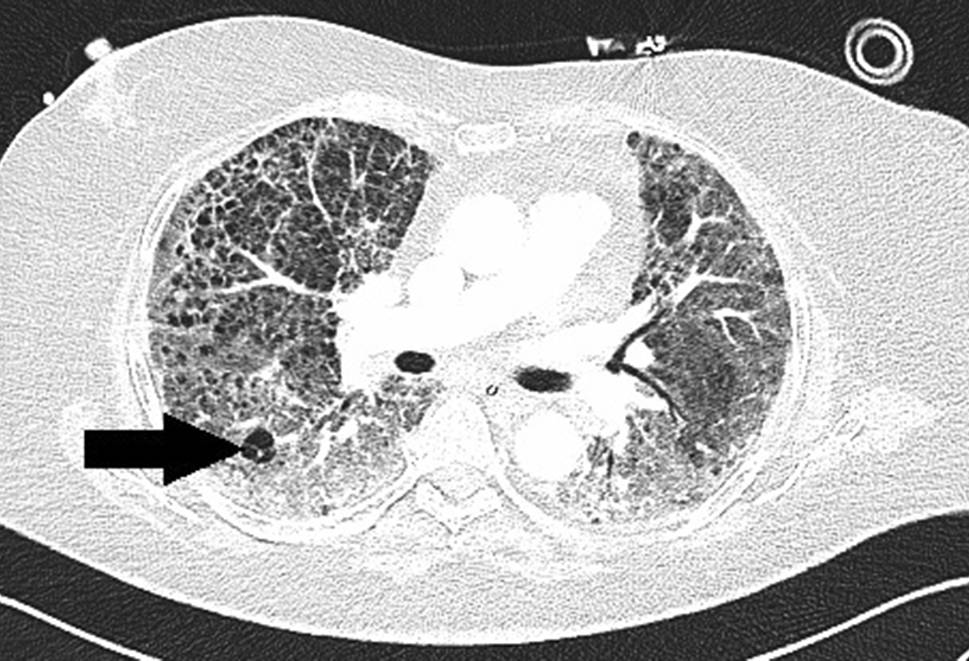

Die Kreislaufparameter waren bis auf leichte Tachykardie von 95/min unauffällig, die Patientin war afebril. Bei erhöhter Atemfrequenz von 28/min betrug die periphere Sauerstoffsättigung 87 % unter 10 l O2/min Maskenatmung. Im Labor bestanden Leukozytose von 9,5 G/l sowie Erhöhung von CRP auf 85,7 mg/l, von Ferritin auf 1062 ng/ml und von (IL)‑6 auf 225 pg/ml. In Thorax-CT zeigten sich bilaterale, diffus flächig konfluierende Milchglasverdichtungen (Abb. 7). Nach Einleitung von antibiotischer Therapie und Kortisongabe gelang es zunächst mit nichtinvasiven Beatmungsverfahren, einen Oxygenationsindex von 150 zu halten. Am Tag 6 wurden jedoch Intubation und Beatmung unumgänglich. Am Tag 13 fand sich erstmals ein Weichteilemphysem links thorakal und rechts supraklavikulär. Die Thoraxröntgenaufnahme (Abb. 8) zeigte zusätzlich zum Weichteilemphysem einen schmalen, apikalen Pneumothorax links, der umgehend drainiert wurde. Danach war das Weichteilemphysem regredient. Nach erfolgreichem Weaning von der Beatmung („dual positive airway pressure“, Spitzrendrücke 30 mbar, durchschnittlicher „driving pressure“ 15 mbar für insgesamt 19 Tage) wurde die Patientin am Tag 26 aus der Intensivbehandlung entlassen und am Tag 54 mit residualem, intermittierendem Sauerstoffbedarf von 3 l/min in die externe Rehabilitation transferiert.

Abb. 7

Bilaterale Lungenfibrose nach COVID-Pneumonie. Pneumatozele im rechten Unterlappen (Pfeil)

Abb. 8

Weichteilemphysem (lange Pfeile), apikaler Pneumothorax links (kurze Pfeile)